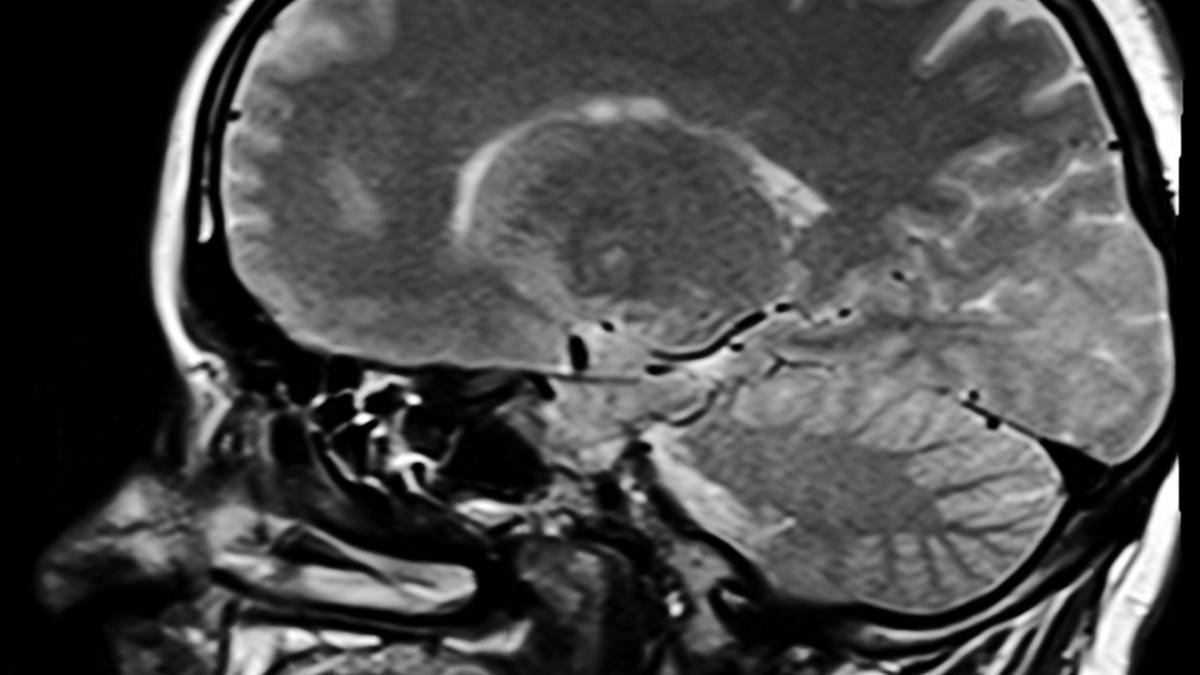

inflamarea-creierului-din-cauza-covid19-seamana-cu-cea-de-la-alzheimer_14963500 Foto cu caracter ilustrativ: Pixabay

Cea mai cuprinzătoare investigație moleculară până în prezent a descoperit acum inflamații extinse și degenerare în creierul celor care au murit din cauza COVID-19 - chiar și atunci când nu au raportat niciun simptom neurologic în timp ce erau în viață. Semnele sunt extrem de asemănătoare cu ceea ce vedem la bolile boala Alzheimer și Parkinson și, cu toate acestea, indiferent cât de greu s-au uitat autorii, nu au putut găsi nicio urmă a virusului real în țesutul cerebral.

În cortexul frontal, care este responsabil pentru luarea deciziilor, memorie și raționament matematic, cei care au murit din cauza COVID-19 au prezentat semne grave de suferință neuronală. Stratul cel mai exterior din această parte a creierului a prezentat diferite modificări moleculare în comparație cu grupul de control, inclusiv suprimarea neuronală crescută și activarea neuronală limitată.